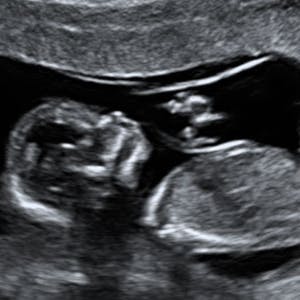

Gravid

Vi gør en dyd ud af at klæde dig godt på både før, under og efter din graviditet. Vi ved, at der kan komme mange spørgsmål til din graviditet, fødsel, amning, din babys udvikling og mange flere emner, derfor har vi samlet guides, tips & tricks samt læsernes egne fortællinger i dette gravid univers.